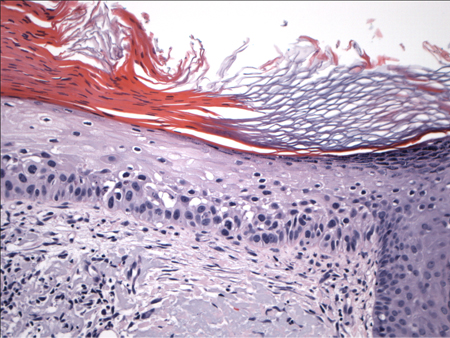

Exibe ceratinócitos atípicos que parecem encher a camada basal e os níveis mais baixos da epiderme, mas não se estendem até a espessura máxima.[Figure caption and citation for the preceding image starts]: Biópsia mostrando a histologia de uma ceratose actínica com atipia de ceratinócitos limitada à camada basalDo acervo particular de Dr. Nwaneshiudu e Dr. Soltani [Citation ends].

Exibe a atipia de espessura máxima que está confinada à epiderme, com uma membrana basal intacta. O envolvimento da espessura inteira da epiderme ocorre em seguida, e há uma camada granular ausente, bem como paraceratose.[Figure caption and citation for the preceding image starts]: Biópsia mostrando a histologia característica de um carcinoma de células escamosas (CCE) in situ com atipia de ceratinócitos de espessura máximaDo acervo particular de Dr. Nwaneshiudu e Dr. Soltani [Citation ends].